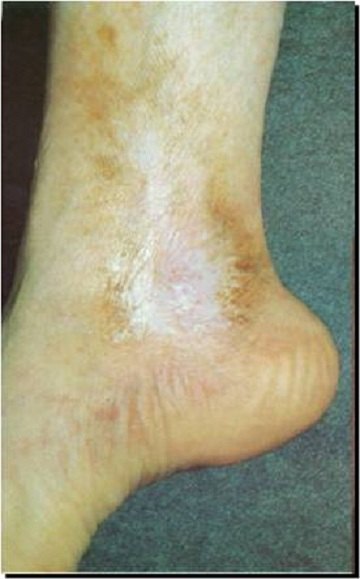

C4 级的患者下肢一般有皮肤的改变(如图4),主要表现有以下几点:

色素沉着,早期一般发生在踝周,皮肤变黑,逐渐向小腿或者足部发展;

皮肤硬化,患者发生下肢静脉曲张的皮肤可能会出现瘢痕、硬化,有时可能有局部的皮肤发红、触痛,但是一般不会发热,这是一种比较严重的皮肤改变;湿疹,足踝或小腿出现水泡或者红斑。病程进展到这一阶段,往往需要积极的外科治疗。

图4- C4 级